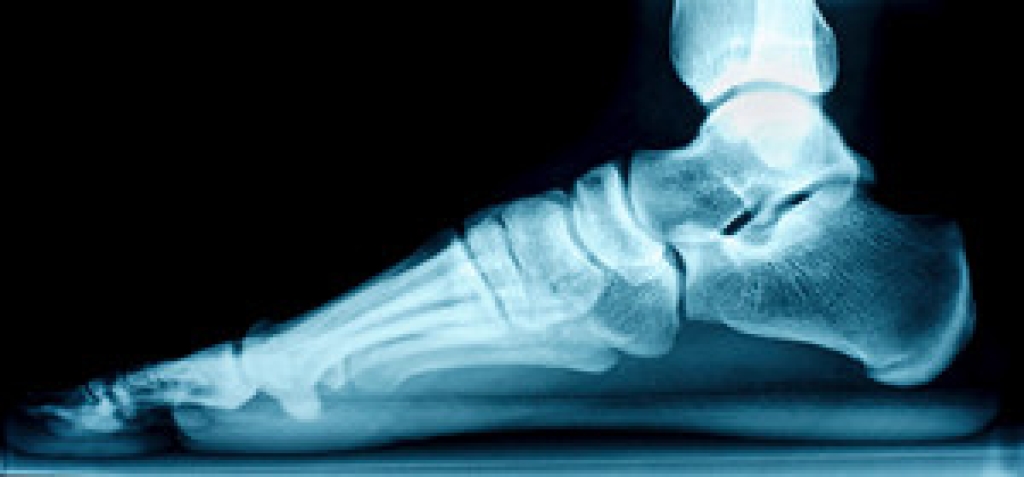

Flat feet is a condition in which the arch, the curved middle part of the bottom of the foot, is absent or has collapsed. The lack of an arch causes the entire sole of the foot to make direct contact with the ground when walking or standing. There are actually two types of flat feet that differ slightly from one another. Flexible flat feet have the ability to form an arch, but this arch flattens when any weight is put on the foot. However, the arch is visible when you are sitting down or holding your foot up in the air. This is the most common type of flat foot. Rigid flat feet cannot form an arch, regardless of whether or not weight is placed on them. While most cases of flat foot do not require medical intervention, sometimes this condition can cause pain or discomfort. In those cases, it is recommended that you see a podiatrist for treatment.

Flatfoot is a condition in which the arch of the foot is depressed and the sole of the foot is almost completely in contact with the ground. About 20-30% of the population generally has flat feet because their arches never formed during growth.

- Flat look to one or both feet